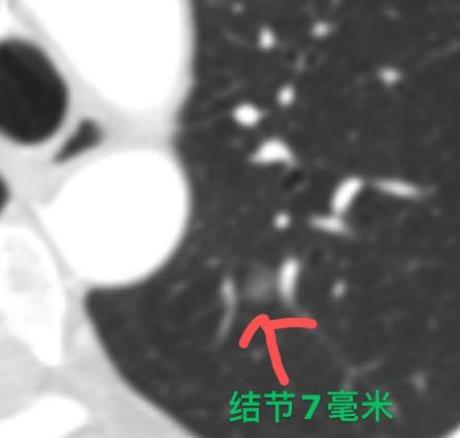

“从查出肺癌到离开,连一年都不到。”诊室里,这位32岁的患者说起家里的情况,眼圈一下就红了。 她的父亲和伯父都是因为肺癌去世的,所以当她发现自己肺上有个7mm的磨玻璃结节时,整个人都紧绷着,一再要求尽快手术。 其实她的结节已经随访半年了,大小形态一点没变,从影像上看,边缘很光滑,密度也均匀,大概率是原位癌或者微浸润癌,还属于非常早期的阶段。 像这样的结节,很可能八到十年都不会进展,本来我建议继续观察就好。而且它长得位置比较深,不像那些靠近肺外周的结节,做个简单的楔形切除就能解决。 但她因为这个结节,每天吃不好、睡不好,工作也受影响。和丈夫反复商量后,她态度还是很坚决:一定要做手术。 于是我们术前做了详细的三维重建规划,争取只做亚段切除——用尽可能小的范围,完整拿下结节。最后术中病理证实是“微浸润腺癌”,淋巴结也没有转移,手术完基本上就算治愈了。 处理肺结节,我一直坚持一个原则:尽量把损伤降到最低!如果为了一个长期稳定的小结节,盲目切掉整个肺叶,那不仅得不偿失,还会严重影响以后的生活质量。这种情况下,继续观察往往是更好的选择。 但如果能在精准评估后,只切一小部分肺就解决问题——比如做个亚段切除或楔形切除,同时让患者放下心理负担、恢复正常生活,那么手术也是值得考虑的选择。[作揖][玫瑰]